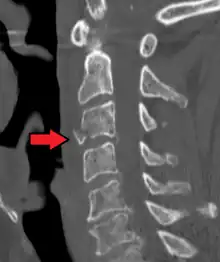

| A fracture of the base of the dens (a part of C2) as seen on CT. | |

On CT scan or X-ray, a cervical fracture may be directly visualized. In addition, indirect signs of injury by the vertebral column are incongruities of the vertebral lines,[7] and/or increased thickness of the prevertebral space:[8]